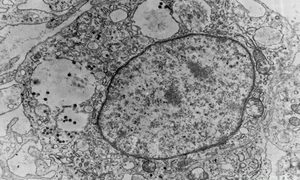

トリ白血病ウイルス(Avian leukosis virus) ~ トリ白血病

トリ白血病ウイルス(ALV)はレトロウイルスで、世界中のニワトリに数種類の良性・悪性新生物(腫瘍)を発生させる原因となります。ALVには7つの異なる亜群(subgroups)(A~J)がありますが、J亜群は群れの間で発生する最も重要な原因と...